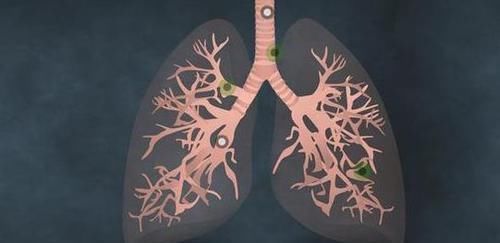

日常生活中,倘若你感觉自己的呼吸十分急促,那么还请提高警惕。这种情况的出现,是由于肺癌肿瘤已经影响到了呼吸系统,从而让呼吸通道出现了堵塞,这样就让空气无法顺畅地进入到体内,最后让患者出现呼吸困难的情况。另外当肺癌细胞组织,入侵到了体内的一些淋巴细胞组织,甚至是静脉血管,那么也是很容易会引起呼吸困难的情况出现。